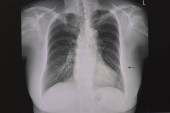

RTG klatki piersiowej pacjenta po lewej torakotomii płuc (chirurgiczne usunięcie płuca). Pacjent ma również złamane prawe żebro..

Zdjęcie "RTG klatki piersiowej pacjenta po lewej torakotomii płuc (chirurgiczne usunięcie płuca). Pacjent ma również złamane prawe żebro.." może być wykorzystywane do celów osobistych i komercyjnych zgodnie z warunkami zakupionej licencji Royalty-free. Obraz jest dostępny do pobrania w jakości wysokiej rozdzielczości do 5760x3840.